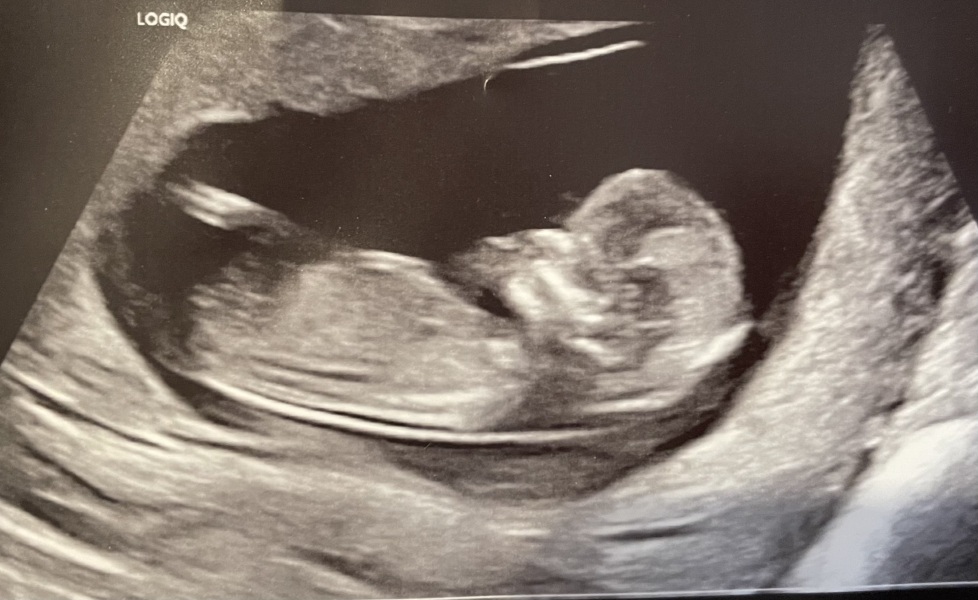

GraySweatpants · 23/10/2024 13:26

@ThatGladSwan Congrats! Looking very cute and healthy.

Here is mine. Anyone can guess boy or girl cuz I can’t 😆

May 2025 Babies